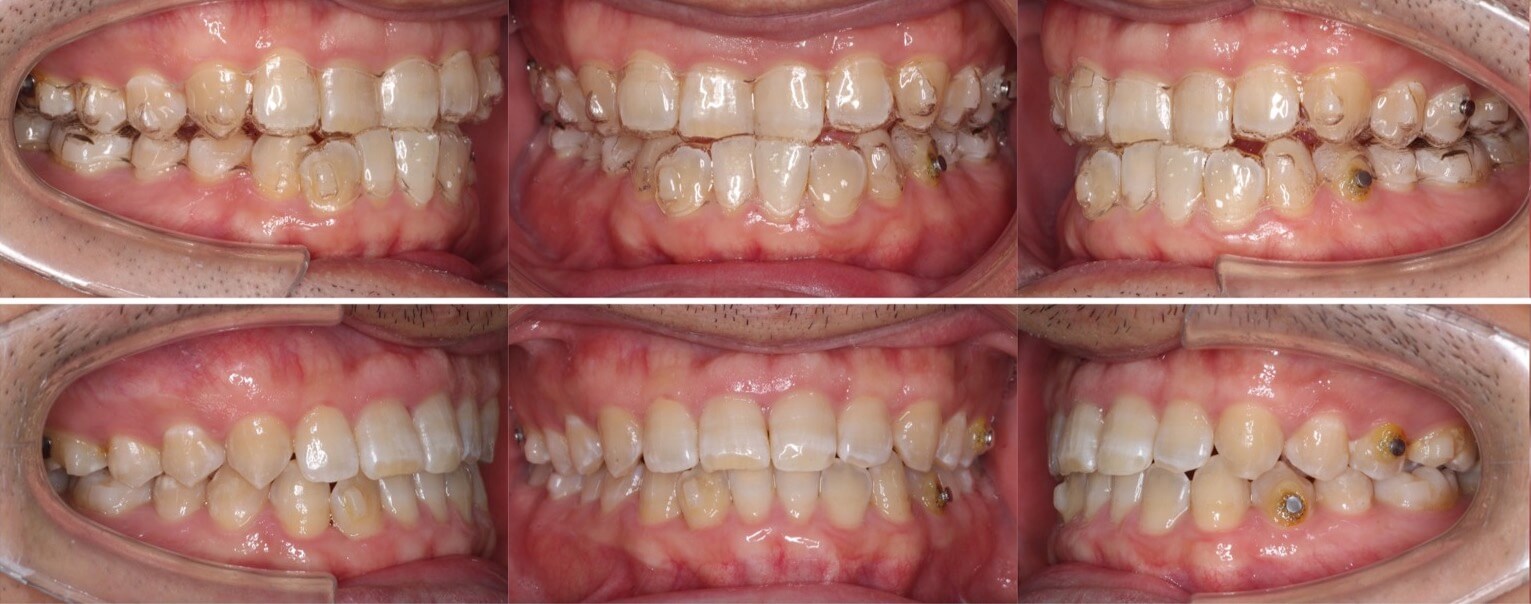

大学生女性・唇側矯正装置・小臼歯4本抜歯

<顔のビフォーアフター>

<症例概要>

主訴:受け口・前歯のガタガタ

年齢・性別:大学生女性

住まい:千葉県八千代市

症状:反対咬合・重度叢生・開咬

治療方針:上下小臼歯抜歯・空隙閉鎖

治療装置:唇側矯正装置

固定装置:上バイヘリックス装置・III級顎間ゴム

抜歯:上第二小臼歯・下第一小臼歯・下親知らず(計6本)

治療期間:2年2か月

リテーナー:上下フィックスタイプ+クリアタイプ

治療費用:968,000(税込)

代表的副作用:痛み・治療後の後戻り・歯根吸収・歯髄壊死・歯肉退縮

歯が並ぶスペース不足が大きく、前歯の不揃いが強いケースです。また、上下の前歯は開咬状態になっており咀嚼障害もあります。上下小臼歯抜歯を行いできたスペースをうまく利用して前歯を並べ、III級顎間ゴムを使用し下の歯列全体を親知らずを抜歯した後方へ起こしました。非常に難しい治療方針でしたが、ご本人がゴムの使用を頑張ってくれたので予定より早く治療期間も終わり、審美的にも機能的にも良い歯並びになりました。